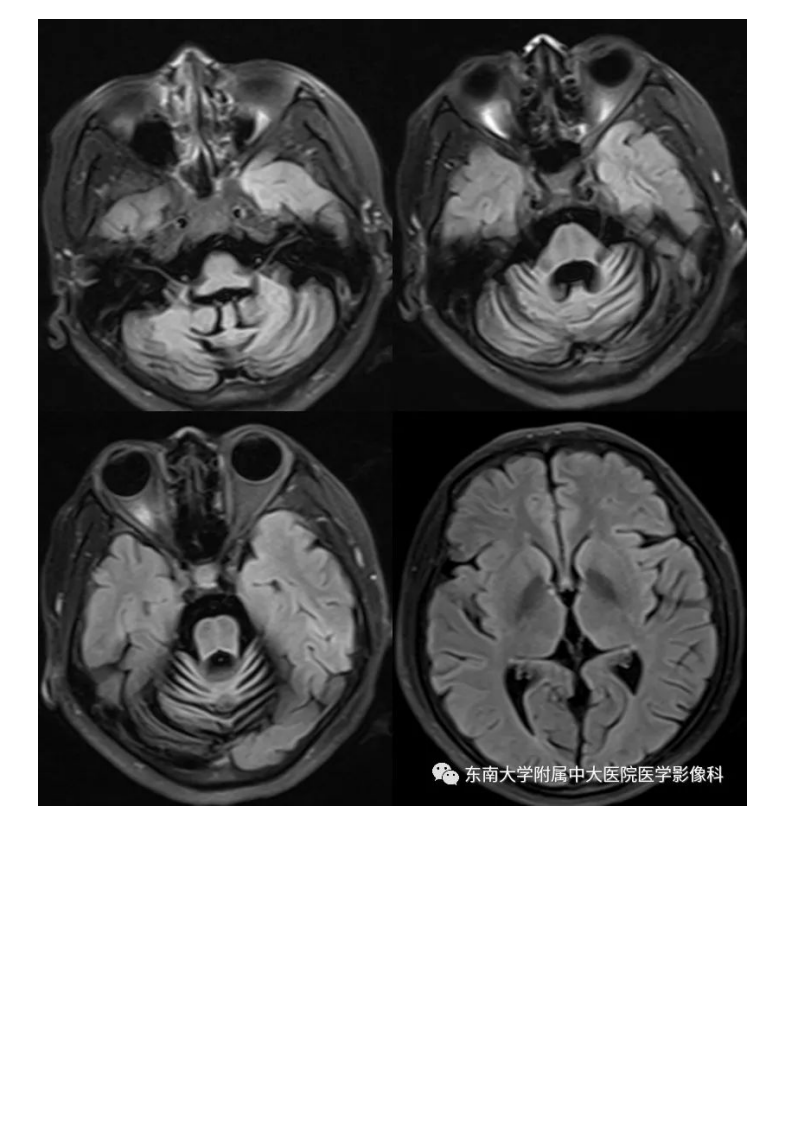

20200928_2【晨读结果公布】2020.09.28神经系统疾病——脊髓小脑性共济失调(病例1).pdf